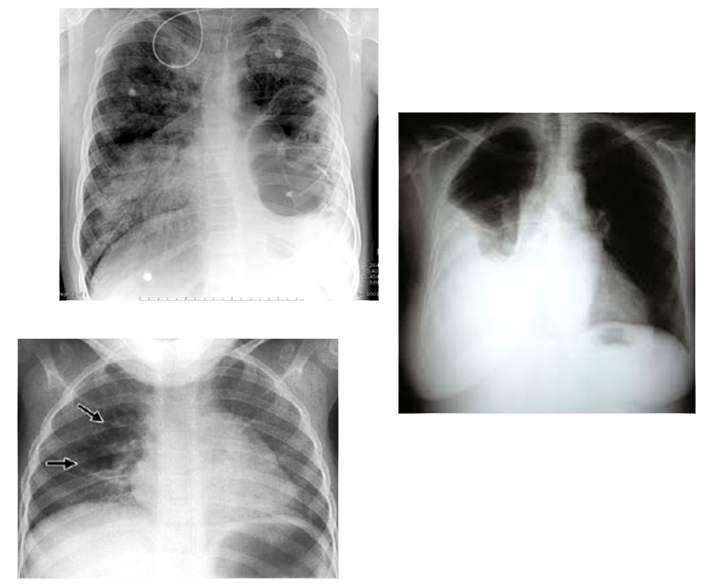

1. RX

1. a) neumonía,clásica o focal, b) bronconeumonía o neumonía multifocal c) neumonía intersticial o atípica,